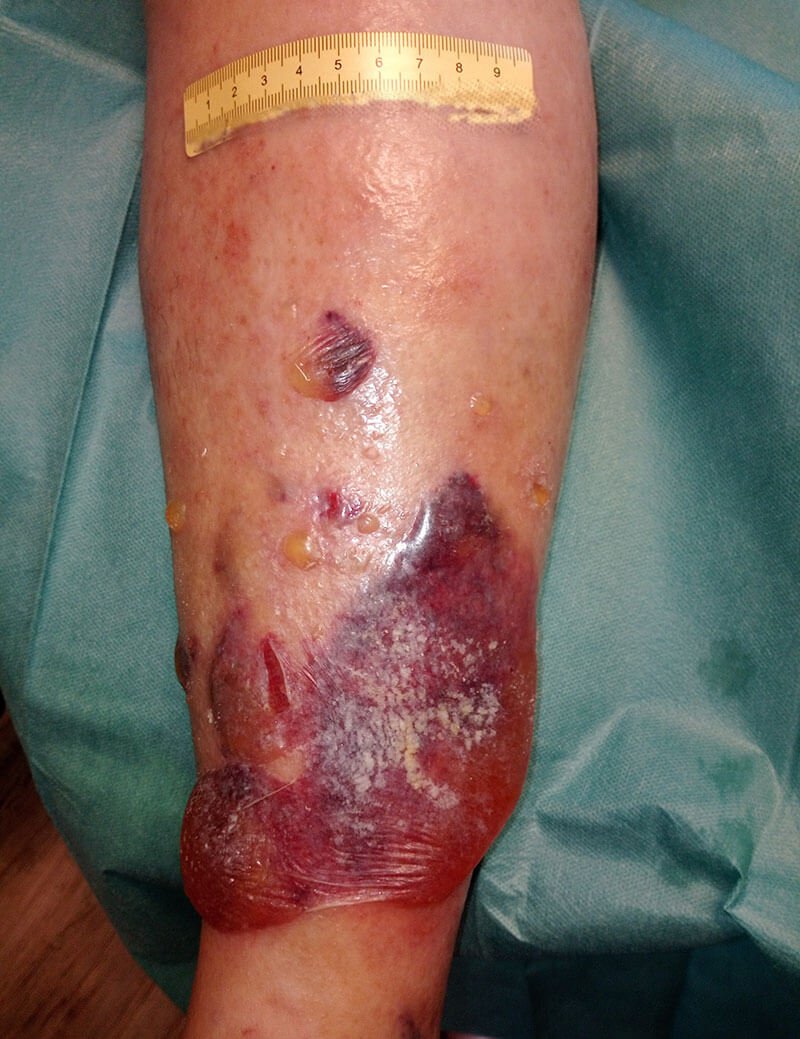

Herr P. kommt in die Praxis mit massiver Blasenbildung, teilweise eröffnet und stark exsudierend bei bekannter CVI. Ursache ist augenscheinlich ein falsch angelegter, verrutschter Kompressionsverband, der zunächst kleine Verletzungen verursachte.

Aktuell lässt sich bei Herrn P. eine beginnende Dekompensation der Herzinsuffizienz feststellen und gleichzeitig ist der Kompressionsverband am linken Unterschenkel nach nicht korrekter Anlage deutlich verrutscht. Es kam dadurch zu kleinen Verletzungen. Die gleichzeitig erfolgte Ödembildung führte zu einer massiven Exsudation und in der Folge zu deutlicher Blasenbildung. Teilweise sind Blasen auch eröffnet, sodass sich Teile der Oberhaut am Unterschenkel ablösen.

Bild 1 zeigt den Befund bei der Vorstellung des Patienten. Nach Entfernung der sich ablösenden Oberhaut (Bild 2) zeigen sich granulierende Wunden am Unterschenkel. An den Wundrändern sieht man, dass sich im Verlauf vermutlich weiter etwas Oberhaut ablösen wird. Die Unterschenkel sind insgesamt leicht ödematös, das gesamte Hautbild ist sehr gepflegt. Die sich ablösende Oberhaut wird abgetragen und die Umgebungshaut wird mit dünn einmassierter Zinkcreme vor der austretenden Exsudation geschützt.